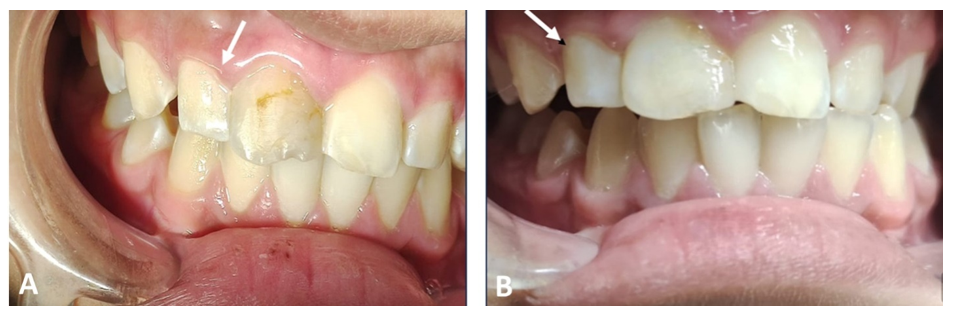

The panoramic radiograph showed a periapical radiolucency between the central and lateral upper right incisors (Teeth # 12 and 11), and a confirmatory periapical radiograph revealed a large, well-defined radiolucency in the periapical region between the two teeth with severely diverged roots (Figure 2).

Figure 2 A panoramic radiograph shows tilted roots of the right lateral incisor due to pressure of the periapical lesion (circle). A preapical radiograph shows a large periapical lesion (14x26mm) with diverged roots of related teeth(# 12 and 11).